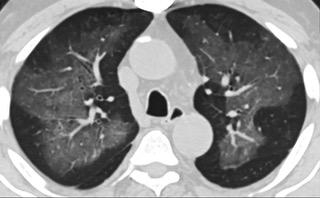

疑点一,电子烟患者的CT影像和临床表现并不具有特异性。所谓美国电子肺炎患者,其实是对没有其他合理诊断证据、吸食电子烟肺炎患者的统称。这些患者在病发前90天内吸食了电子烟,尤其值得注意的是,部分患者的CT影像特征和临床表现与病毒性肺炎患者极其相似。

中、下肺轴位CT平扫显示毛玻璃样混浊伴胸膜下保留。(同一病人CT影像)